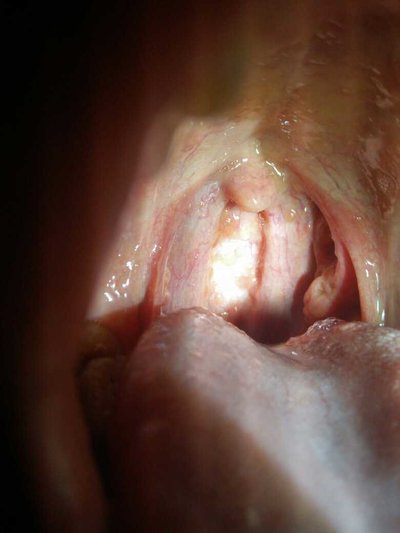

Vocal cord carcinoma is the most common type of laryngeal carcinoma. Most of them are well differentiated carcinoma, but they show infiltrative growth, even if the tumor surface morphology is regular. The growth characteristics of vocal cord carcinoma are determined by its unique anatomy. First of all, the lymphatic drainage of the true vocal cord is very rare except for posterior syndesmosis, so the early lesions rarely have metastasis; Secondly, the tumor on the surface of the vocal cord first diffuses through the elastic membrane in the larynx and invades the vocal cord muscle and the paravocal space, which is the last way for the tumor to pass through the cricothyroid space and get out of the larynx. Vocal cord cancer in the early onset of symptoms, because a slight change in the vocal cord surface can cause changes in sound. It is rare for patients with vocal cord cancer to see a doctor because of cervical lymph node enlargement, and lymph node metastasis occurs in advanced lesions. Vocal cord cancer symptoms? Let's talk about it

The growth characteristics of vocal cord carcinoma are determined by its unique anatomy. First of all, the lymphatic drainage of the true vocal cord is very rare except for posterior syndesmosis, so the early lesions rarely have metastasis; Secondly, the tumor on the surface of the vocal cord first diffuses through the elastic membrane in the larynx and invades the vocal cord muscle and the paravocal space, which is the last way for the tumor to pass through the cricothyroid space and get out of the larynx. With the invasion of the deep tissue, the pathological changes were more serious,

There will be various degrees of movement damage, including subtle mucosal limitation and obvious vocal cord fixation. The degree of limitation of vocal cord movement is significantly related to local control rate and survival rate, which has been used in AJCC staging. The most unique anatomical structure of the vocal cord is the anterior commissure, which is directly connected to the inner surface of the thyroid cartilage plate, and can initially prevent the spread of tumor in the region. If the tumor passes through the ligament barrier of the anterior commissure, the cartilage will be involved. In this case, radiotherapy and surgery should be combined in the selection of treatment options [1,2].

Vocal cord cancer is symptomatic in the early stage of onset, because slight changes in the surface of vocal cords can cause voice changes. However, smokers often have hoarseness, and voice changes may not attract their attention. If the change of voice can not be relieved within a few years, laryngeal examination should be performed, such as indirect laryngoscope, fiber laryngoscope, dynamic laryngoscope, etc. It is rare for patients with vocal cord cancer to see a doctor because of cervical lymph node enlargement, and lymph node metastasis occurs in advanced lesions.